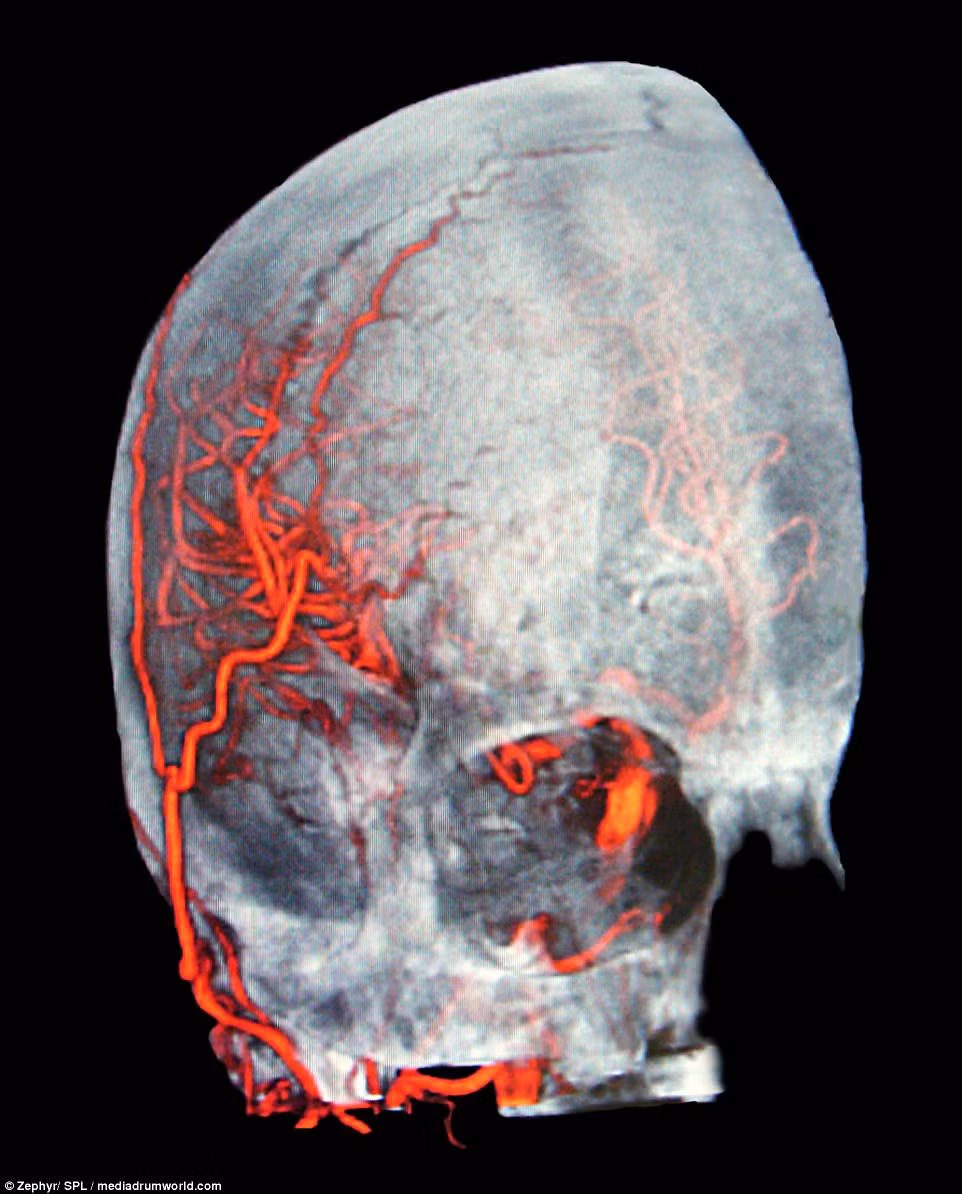

Đây là hình ảnh chụp 3D của hộp sọ, các động mạch, não và mặt của một bệnh nhân để đánh giá về xuất huyết dưới màng nhện khi bệnh nhân bị phình mạch máu. Xuất huyết dưới màng nhện là một dạng đột quỵ hiếm gặp vì gây chảy máu trên màng não.